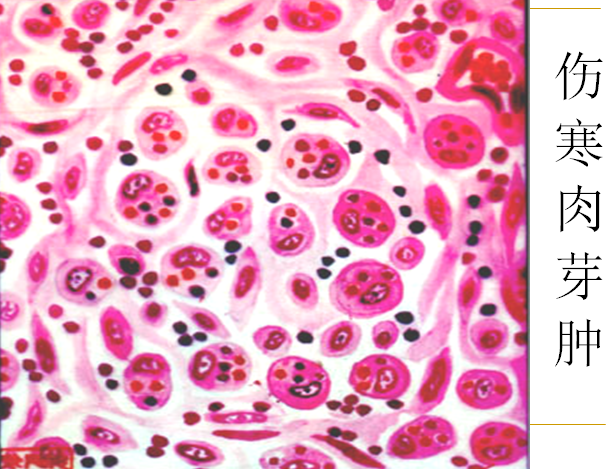

伤寒杆菌引起的炎症是以巨噬细胞增生为特征的急性增生性炎。主要形成具有特征性的伤寒肉芽肿。

伤寒细胞(重点!):增生活跃时巨噬细胞质内吞噬有伤寒杆菌、红细胞和细胞碎片,而吞噬红细胞的作用尤为明显。这种巨噬细胞称伤寒细胞。

伤寒肉芽肿(重点!)(typhoid granuloma):伤寒细胞常聚集成团,形成小结节称伤寒肉芽肿或伤寒小结(typhoid nodule),是伤寒的特征性病变,具有病理诊断价值。